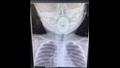

نجح فريق طبي بمستشفى إهناسيا التخصصي ببني سويف، اليوم الجمعة، في إنقاذ حياة طفلة من الموت المحقق، بعد استخراج جسم معدني عالق بمجرى التنفس.

وأوضح الدكتور عبدالله أسامة مدير المستشفى، أن قسم الطوارئ استقبل طفلة عمرها عام واحد، مصابة بصعوبة بالتنفس، ونقص فى نسبة الأكسجين بالدم، فجرى التوجيه على الفور بعمل الإسعافات الأولية لإنقاذ الحالة، وبإجراء الفحوصات الطبية والأشعة اللازمة لها، تبين وجود جسم غريب يسد مجرى التنفس.

وأضاف أن فريقا طبيا بقيادة الدكتور عبد الهادي محمد أخصائي الأنف والأذن والحنجرة، نجح في إنقاذ حالة الطفلة واستخراج الجسم المعدني، والذي يبلغ قطره 3 سم، و طوله 6 سم.